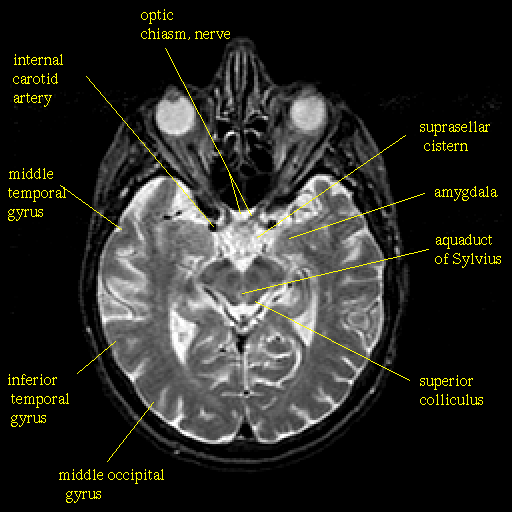

T2-weighted structural MR: Slice 23

Slice 23